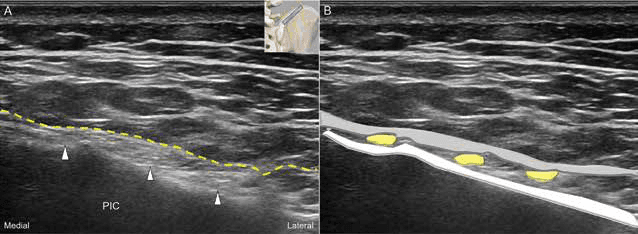

흉요근막을 표적으로 하는 측면-내측 평면내 접근법을 통해 효과적인 수압박리술을 수행했습니다. 수압박리술 - 그림 10. 흉요근막을 목표로 하는 평면내(lateral to medial) 접근법(A)입 Figure 10. 그림 10. 흉요근막을 목표로 하는 평면내(lateral to medial) 접근법(A)입니다. 해당하는 개략도(B)입니다.

장골능 상연을 목표로 하는 평면내 접근법으로 수술 후 진통에 효과적인 수압박리술을 시행했습니다. 수압박리술 - 그림 11. 장골능(iliac crest) 상연을 목표로 하는 평면내(lateral to Figure 11. 그림 11. 장골능(iliac crest) 상연을 목표로 하는 평면내(lateral to medial) 접근법(A)입니다. 해당하는 개략도입니다.